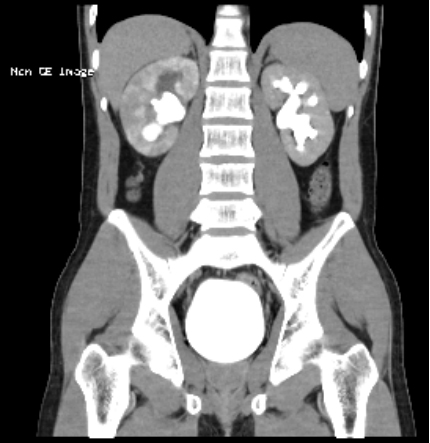

术前泌尿系CT(冠状位)

患者8年前因腹痛检查发现双肾结石、右输尿管结石,曾于当地行体外碎石治疗,未规律随访;后于2014年行输尿管镜取石治疗;2018年行左侧经皮肾镜取石术,后复查残石较多;患者9天前再次出现右侧腰腹部疼痛,伴发热,遂于当地治疗,仍反复发热,CT检查显示“双肾结石、右侧输尿管结石并上游尿路扩张积水”。